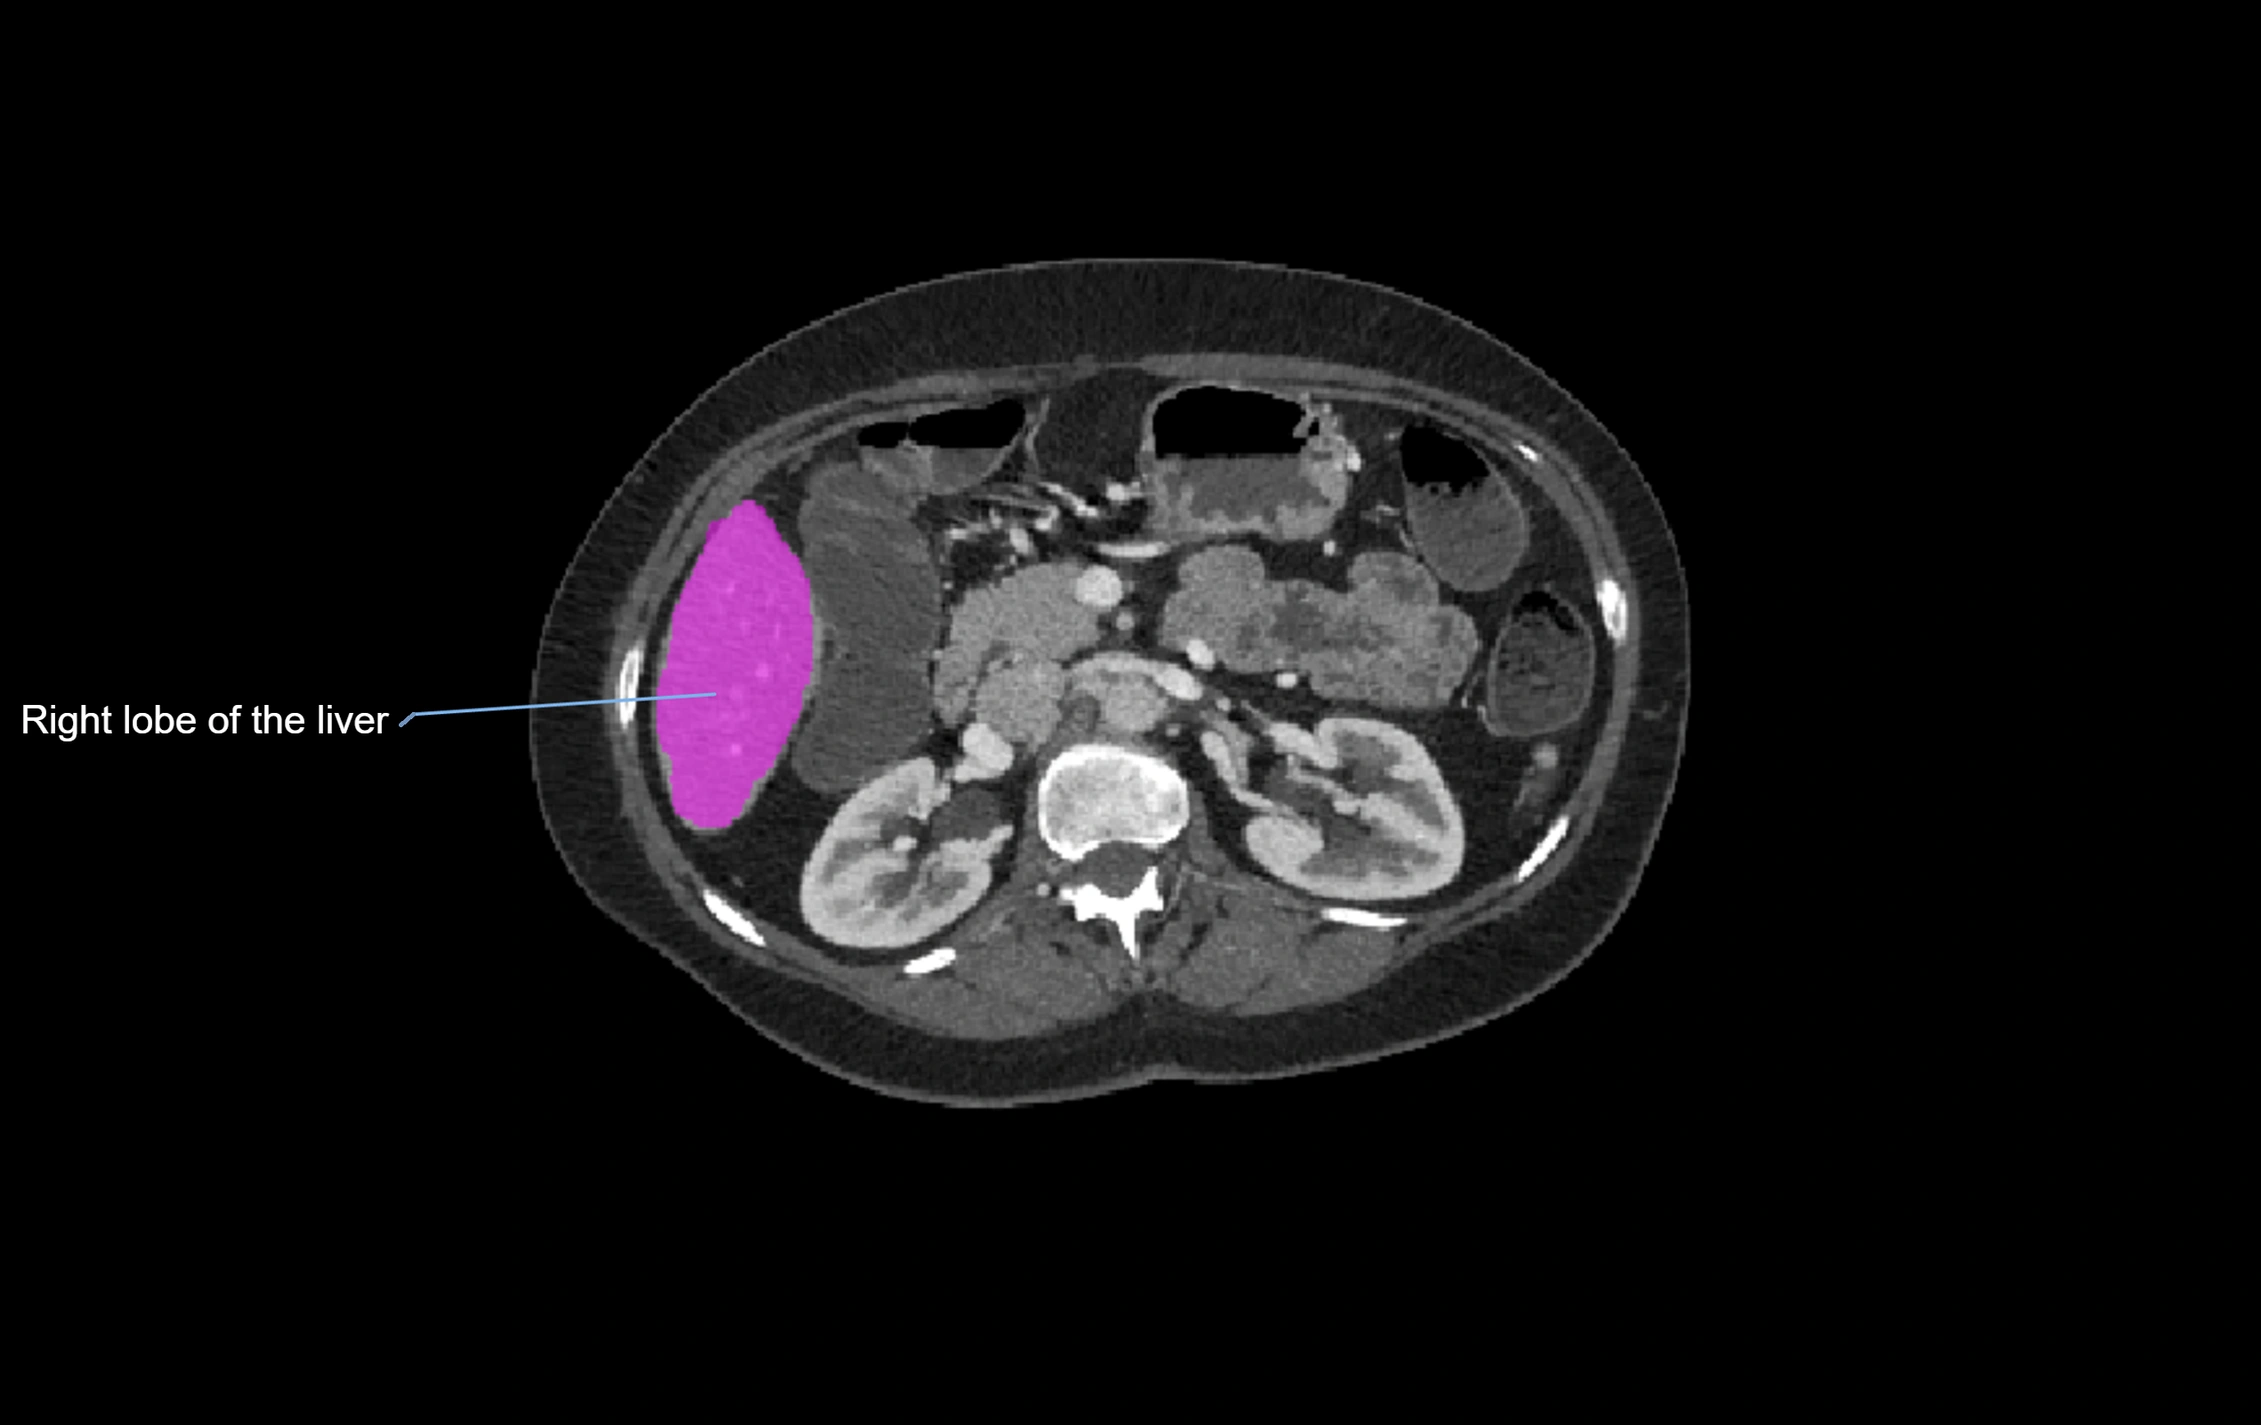

CT Pre-Contrast:

• Caudate lobe appears as a soft-tissue density, isodense to the rest of the liver

• Enlargement may be appreciated in cirrhosis or Budd–Chiari syndrome

image

CT Image